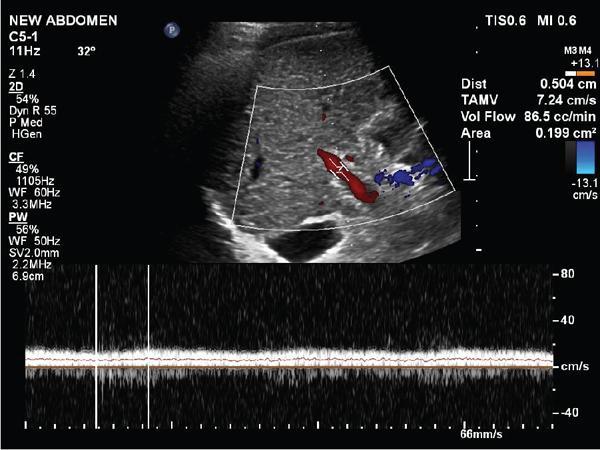

Shrinivas B. Desai, Ritu K. Kashikar, Aman Snehil, Ajay Jhaveri Cirrhosis is a late stage of irreversible scarring of the liver causing abnormality in liver structure and function. Multiple conditions and factors can cause repeated liver damage and scarring ultimately leading to cirrhosis. The most feared complication of liver cirrhosis is the development of hepatocellular carcinoma (HCC). Portal hypertension (PHT) is seen with a variety of conditions but cirrhosis happens to the most important cause. Imaging plays a vital role in noninvasive diagnosis and treatment planning of both cirrhosis and PHT. Liver imaging reporting and data system (LI-RADS) is a standardized reporting system assigning an observation risk of representing HCC. This chapter focuses on discussing aetiologies and imaging of PHT with a lucid review of L1-RADS 2018 version. The portal blood circulation is a unique circulatory circuit as it connects two capillary beds between the liver parenchyma at one end and the gastrointestinal tract and splenic parenchyma at the other end. The portal system ramifies in the liver and ultimately ends in the hepatic sinusoids from where the blood ultimately drains into the inferior vena cava (IVC). The portal vein (PV) originates from the capillary beds in the stomach, intestine and the spleen. The main PV is formed behind the neck of the pancreas by the confluence of the superior mesenteric vein (SMV) and splenic vein. It continues to the porta hepatis where it bifurcates into the left and right branches as it carries nutrient rich but oxygen poor blood to the liver (Fig. 9.9.1). The PV makes up for 75%–80% of the liver’s blood supply while the hepatic artery which arises from the celiac trunk makes up for the remaining 25%. A pathological increase in the portal venous pressure is referred to as PHT. PHT is most often a sequel of chronic parenchymal liver disease and leads to major life-threatening complications due to bleeding from the collateral circulation (most commonly oesophageal varices). Direct measurement of portal pressure (PP) is invasive and often not feasible in most patients and thus imaging plays an important role in the diagnosis of PHT and its complications. The normal portal venous pressure ranges between 5 and 10 mmHg, which is the equivalent of 7–14 cm H2O. The normal hepatic venous pressure gradient (HVPG) is the pressure gradient between the PV and the IVC, is typically 1–5 mmHg. Presence of PHT is indicated by a wedged hepatic venous pressure of more than 5 mmHg. Other definitions include a splenic pressure of more than 15 mmHg or an intraoperative PP of greater than 30 cm H2O. The complications of PHT are seen when HVPG is greater than 10 mmHg and hence this value defines clinically significant PHT. Variceal bleeding is seen with a pressure greater than 12 mmHg. In ideal conditions, the portal circuit is a high flow, low resistance circuit as it has to allow substantial flow rates of 700–1000 mL/min to the hepatic parenchyma from the gastrointestinal tract. Anatomical changes in the organization of the hepatic lobule can result in rise in the portal resistance. These can occur in the form of collagen deposition in the space of Disse, fibrotic scars formed due to regenerative nodule (RN) formation, loss of normal elasticity of the endothelium and distal venous thrombosis. Changes in splanchnic haemodynamics due to factors that increase splanchnic blood flow and increase in intrahepatic vascular resistance due to transformation of stellate cells into myofibroblasts also contribute to the increase in PP gradient. In Western countries, alcoholic cirrhosis and viral cirrhosis are the leading causes of PHT and oesophageal varices. The viral causes form majority of cases leading to cirrhosis and PHT in the Far East and Middle Eastern countries while Schistosomiasis remains an important cause in the African countries. Worldwide, nonalcoholic steatohepatitis (NASH) and hepatitis C are the emerging causes of chronic liver disease (CLD) and PHT. PHT can be classified as cirrhotic and noncirrhotic depending on whether it is associated with cirrhosis or not. This distinction is important as noncirrhotic causes like PV thrombosis are at high risk of development of bleeding but tend to have a better chance of surviving a variceal bleed than a patient with decompensated alcoholic cirrhosis due to preserved hepatic synthetic functions in the former. PHT can also be classified on the basis of the location of the pathology into prehepatic, hepatic and posthepatic causes. Hepatic causes can further be divided into presinusoidal, sinusoidal and postsinusoidal. The causes of portal hypertension have been denoted in Table 9.9.1. The direct measurement of the PP by measuring the HVPG is invasive, expensive not readily available in all patients. Thus, imaging plays an important role in the diagnosis of PHT. Various modalities are used for the imaging diagnosis of PHT. Ultrasonography (USG) and Doppler evaluation have the advantage of being inexpensive, readily available and bedside modality (Table 9.9.2). The role of ultrasound and Doppler in imaging of PHT is to: Grey scale imaging is useful in evaluating the splenoportal anatomy. The evaluation should begin with the liver morphology. Signs of cirrhosis like nodularity of the liver surface with relative atrophy of the right lobe and prominence of the left lobe and caudate should be looked for. Hepatic echotexture appears coarse and more echogenic (Table 9.9.3). Increase in portal venous diameter is a sign of PHT (Fig. 9.9.2). Portal venous diameter of more than 13 or 15 mm has low sensitivity for diagnosing PHT of only 40%–12.5%, respectively. Absolute measurement of the portal diameter as a sign of PHT is also fallacious as in presence of collateral circulation or hepatofugal flow; there may actually be a decrease in the PV diameter. Therefore, a more accurate sign is respiratory variation of PV diameter. An increase in PV diameter of less than 20% with deep inspiration has been reported to indicate PHT with a sensitivity of 80% and specificity of 100%. This has been reported to be an accurate indicator of cirrhosis. Hepatic vein straightness, uniformity of vein wall echogenicity and visualization of at least 1 cm segment of the hepatic vein are the parameters used for evaluation. Splenomegaly is defined as bipolar splenic diameter of greater than 12 cm or largest splenic cross-sectional area passing through the hilum of greater than 45 cm2, and occurs secondary to PHT (Fig. 9.9.3). A total of 65%–80% patients with cirrhosis have splenomegaly on ultrasound. Patients with cirrhosis due to viral hepatitis and primary biliary cirrhosis show splenomegaly more frequently than those with alcoholic cirrhosis. This is an accurate sign of PHT. USG is extremely sensitive with respect to detecting subclinical ascites. Perihepatic space is the most usual site of visualization of minimal ascites. In normal subjects, this ratio is approximately 0.07 and a value above 0.1 suggests the diagnosis of PHT with a 95% sensitivity and specificity. The normal spectral waveform of the hepatic artery is a low resistance flow pattern with forward flow in diastole and a resistivity index in the range of 0.5–0.7. In PHT, the resistivity index of the hepatic artery increases with high resistance flow pattern due to increased peripheral vascular resistance. Resistance index (RI) > 0.78 in the intrahepatic branches of the hepatic artery has been reported to have a sensitivity of 50% and a specificity of 100% for the detection of PHT (Fig. 9.9.11). Pulsatility index (PI) > 1.05 suggests severe PHT with a sensitivity of 86% and specificity of 88% (Fig. 9.9.11). Patency of hepatic veins should be evaluated to rule out Budd–Chiari syndrome as a cause of PHT. The normal hepatic venous waveform (HVW) reflects right atrial activity and this results in a triphasic waveform with one positive and two negative waves. In PHT, this waveform becomes monophasic or biphasic. A monophasic HVW has a sensitivity and specificity of 74% and 95%, respectively, in the diagnosis of severe PHT (Fig. 9.9.12). Dilatation of the splanchnic veins – the SMV and the splenic vein – more than 11 mm are suggestive of PHT with a sensitivity and specificity of 72% and 100%, respectively. A reduction in the respiratory variation of the splenic vein and SMV to less than 40% had a sensitivity and specificity of 79.7% and 100%, respectively, for the diagnosis of PHT (Fig. 9.9.13). The splenic artery reveals an increase in the resistivity index and an RI of >0.63 and a PI of >1 have a sensitivity and specificity of 84.6% and 70.4% for the diagnosis of PHT. Presence of portosystemic collaterals like patent paraumbilical vein, dilated left gastric and short gastric veins are 100% specific sign for PHT (Figs. 9.9.14–9.9.16). Recanalization of the paraumbilical vein, known as the Cruveilhier–Baumgarten syndrome is observed in 43% of patients with PHT, and this is the easiest collateral to assess during the US examination. Various portosystemic collaterals that occur in PHT have been discussed in details in subsection on CT findings in PHT. No Doppler parameter is considered reliable enough to measure PP with sufficient accuracy for use in clinical practice. Oesophageal varices are often present in patients with portosystemic collaterals. Appearance or increase in number of collaterals along with splenomegaly has a high association with variceal formation and growth. USG helps in diagnosis of prehepatic causes like portal stenosis or thrombosis by demonstrating the patency and morphology of the splenoportal system. Arteriovenous fistulae and tumours causing vascular thrombosis as aetiology can be readily detected. USG helps in diagnosis of features of cirrhosis and thus helps differentiate noncirrhotic causes of PHT. USG allows diagnosis of fatty liver disease, which is an emerging cause of cirrhosis. Among the posthepatic causes, USG aids in establishing the diagnosis of Budd–Chiari syndrome by demonstrating the patency and morphology of the IVC and hepatic veins. Owing to the inability of CT to detect flow direction, portal flow rates or pressure gradients, CT is not the primary modality in diagnosis of PHT. Similar to USG dilatation of portosystemic system is a feature of PHT (Fig. 9.9.17). Changes in cirrhosis if present can be seen in the form of surface nodularity, nodules and fibrous septae. CT plays an important role in diagnosis of portal venous thrombosis and evaluating its extent. An acute thrombus is seen as a hypodense filling defect in the vessel causing distension of the venous lumen. Surrounding fat stranding can be seen. A chronic thrombus appears as an eccentric filling defect usually along the wall and is often associated with decrease in vessel diameter. Calcification may be seen in chronic thrombi. Multidetector computed tomography (MDCT) is a useful tool to evaluate portosystemic collateral circulation and recognize complications of PHT. 3D angiography can help understand portal venous and complex variceal anatomy and plan treatment. The various portosystemic collaterals are discussed below. They can be classified into those draining into superior vena cava (SVC) and those draining into the IVC. Magnetic resonance imaging (MRI) is a noninvasive modality used in the evaluation of PHT without the use of ionising radiation. It provides evaluation of parenchymal abnormalities, collaterals and characterization of tumours (Fig. 9.9.28). Spin echo sequences allow characterization of liver masses and liver parenchyma. Loss of flow void allows for detection of thrombosis. Time-of-flight (TOF) angiography is useful in assessing the portal venous system and allows for successful detection of PV thrombosis. The disadvantages of TOF are motion artefacts caused by breathing, long acquisition times and incomplete coverage of the portal venous system. Novel imaging techniques include phase contrast, T1 mapping and magnetic resonance elastography (MRE). The advantage of phase contrast over TOF imaging is that phase contrast imaging acquires information regarding the flow direction in addition to the information regarding the flow velocity. On-phase contrast images signal within vessel is hyperintense when flow is cranial and hypointense when flow is caudal. Look-Locker imaging technique using gradient echo (GRE) MRI sequences with inversion recovery pulse is used to quantify fibrosis by measuring precontrast T1 relaxation times. Interventions in PHT can be aimed at diagnosis or more commonly at management of complications of PHT. HVPG measurement, which is the gold standard for the diagnosis of PHT, can be achieved through cannulation of the PV. Transjugular hepatic biopsy is another diagnostic invasive technique that also allows indirect measurement of PP. Disadvantages include deterioration of hepatic function caused by diversion of portal venous blood flow and shunt dysfunction. TIPSS is contraindicated in patients with congestive heart failure, severe pulmonary hypertension, severe tricuspid regurgitation and hepatic failure. In this technique, a catheter is advanced from the femoral vein into the outlet of the gastrorenal, usually in the region of the left renal vein. The shunt is then occluded with a balloon and sclerosant is injected retrograde to occlude the gastric varices. Histological development of RNs surrounded by fibrous septae in response to chronic liver injury, progressing PHT and end-stage liver disease is termed as cirrhosis. Although initially considered an end-stage phenomenon in CLD, recent evidence suggests that the histological fibrosis can be reversible in early stages with the initiation of specific therapies, for example, in viral cirrhosis with the initiation of antiviral therapy. The one-year mortality rate in cirrhosis varies widely from 1% to 57% depending on the occurrence of complications. Cirrhosis can have a wide variety of causes ranging from congenital to acquired and infectious to noninfectious. It is also a major aetiologic risk factor for the development of HCC. Imaging plays an important role in aetiologic diagnosis of this diverse entity as well as in the diagnosis and management of its complication and surveillance for oncological transformation.

D. Splanchnic veins